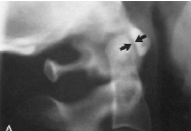

Q what is the name of this measurement? and what is the average + range?

A: Atlantodental Interspace (ADI)

assesses the integrity of the transverse ligament. Average and range for Adults: 1-3 mm. Average and range for Children: 1-5 mm